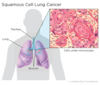

Quais os tipos de carcinoma broncogênico de localização CENTRAL?

EPIDERMOIDE e PEQUENAS CÉLULAS

Um tumor pulmonar que se apresenta com HEMOPTISE e SINTOMAS OBSTRUTIVOS é mais provavelmente que tipo?

CENTRAL

(Epidermoide ou Pequenas células)

Qual o carcinoma broncogênico central mais comum?

CARCINOMA DE CÉLULAS ESCAMOSAS

(EPIDERMOIDE)

É o 2º CA pulmão mais comum, sendo o mais comum central

Quais os tipos de carcinoma broncogênico mais propensos à CAVITAÇÃO?

CA CÉLULAS ESCAMOSAS (EPIDERMOIDE)

e

CA GRANDES CÉLULAS